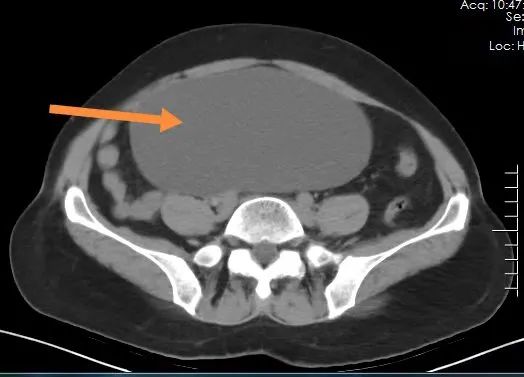

南丹县人民医院妇科又一次在腹腔镜下成功切除盆腔巨大肿瘤近日,南丹县人民医院妇科在腹腔镜下成功切除盆腔巨大肿瘤,肿瘤重达3000g(6斤)。患者病情评估患者莫阿姨(化名),女,52岁,诉8个月前开始出现下腹部隐痛、坠胀不适,并自觉腹部逐渐增大,但未进行诊治,直至腹痛突然加重后到我院进行就诊。就诊医生检查发现患者腹部膨隆如孕6个月,腹部包块上界达脐上2横指,压痛明显,结合CT检查,初步判断为腹...

经过多年的技术积淀,南丹县人民医院妇科形成了一系列的特色诊疗技术,给我县广大妇女疾病的诊疗带来了健康福音,特别是微创技术的进步在很大程度上减轻了患者的痛苦,减轻患者的经济负担,该项技术的创新,使得微创更趋于无创,也标志着我院微创技术的又一提升!目前,我院妇科年手术量达500多例,微创手术率高达98%,可以满足服务我县30多万人口及周边部分市县女性患者的诊疗需求,让许多家庭和妇女...